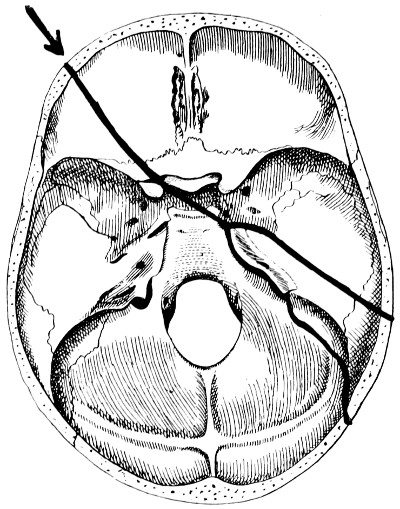

| 28. Illustrating the lines along which forces received on the vault are transmitted to the base | 69 |

| 29 A and B. The base of the skull and the base as seen on transillumination | 70, 71 |

| 30. Plan of the base of the skull | 77 |

| 31. To illustrate the relation of basic fractures to cranial nerves | 81 |

| 32-37. The lines pursued by basic fractures | 83-8 |

| 50 A and B. The inner aspect of the skull and the same seen on transillumination | 137 |